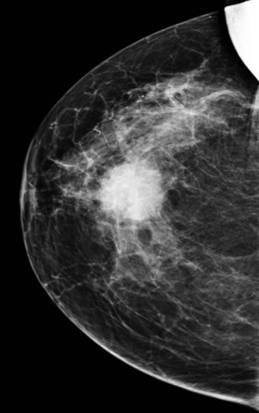

Ung thư vú

» Thông tin: Nữ giới – 76 tuổi.

» Lâm sàng: Khối tuyến vú.